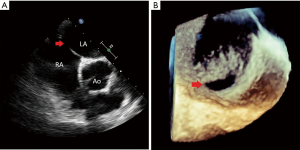

A 49-year-old female with a history of multiple strokes without evidence of atrial fibrillation or carotid disease presents for evaluation. 2D-TTE was suggestive of a patent foramen ovale (PFO), and she was referred for PFO closure with RT3D-TEE. Intra-procedure interrogation of the interatrial septum by 3D-TEE revealed a 9 mm secundum ASD with bidirectional shunting as opposed to a PFO (Figure 3). This information directly influenced device closure selection, and a 10 mm ASO device was selected. In a similar manner to patient #1, after correctly illustrating this patient’s atrial septal pathology, RT3D-TEE was used to ensure appropriateness of rim tissue to accommodate the ASO device. Post-deployment, 3D-TEE exhibited excellent device seal and purchase of all rim tissue without encroachment anteriorly in the aorta (Figure 4).

A 35-year-old male without past medical history developed progressive chest pain and shortness of breath. Workup was negative for myocardial ischemia, but 2D-TTE showed significant right ventricular enlargement and moderate pulmonary hypertension. Also noted on 2D-TTE imaging was a secundum ASD with an estimated maximum diameter of 34 mm (Figure 5). The patient was then referred for percutaneous ASD closure. Pre-procedural 3D-TEE was performed and disclosed the true extent of this large atrial defect, measuring 42×33 mm (Figure 6). 3D images showed minimal rim tissue for device deployment and capture; 3D-TEE clearly revealed that this defect was not amenable to percutaneous closure. Therefore, the patient was referred to surgery and underwent a successful open surgical repair of the large secundum defect.